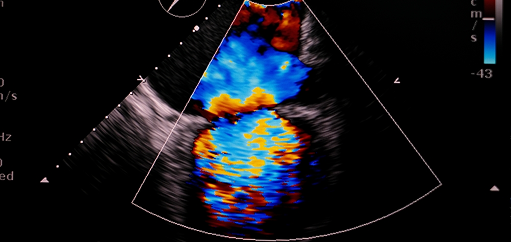

Η μιτροειδής βαλβίδα δεν κλείνει σωστά, με αποτέλεσμα το αίμα να επιστρέφει στον αριστερό κόλπο. Προκαλεί δύσπνοια, κόπωση και καρδιακή ανεπάρκεια. Ανάλογα με τη βαρύτητα, αντιμετωπίζεται συντηρητικά ή με επεμβατικές τεχνικές.

Η τριγλώχινα βαλβίδα παρουσιάζει διαφυγή αίματος προς τον δεξιό κόλπο, επιβαρύνοντας τη δεξιά καρδιά. Μπορεί να προκαλέσει πρήξιμο στα πόδια, ηπατική συμφόρηση και κόπωση. Η θεραπεία μπορεί να περιλαμβάνει επεμβατική αποκατάσταση ή αντικατάσταση.

Η στένωση ή ανεπάρκεια της αορτικής βαλβίδας δυσκολεύει τη ροή του αίματος από την καρδιά προς το σώμα. Προκαλεί κόπωση, δύσπνοια ή ζάλη. Η έγκαιρη διάγνωση και επεμβατική παρέμβαση, όπως η διακαθετηριακή αντικατάσταση βαλβίδας (TAVI), μπορεί να αποτρέψει σοβαρές επιπλοκές.